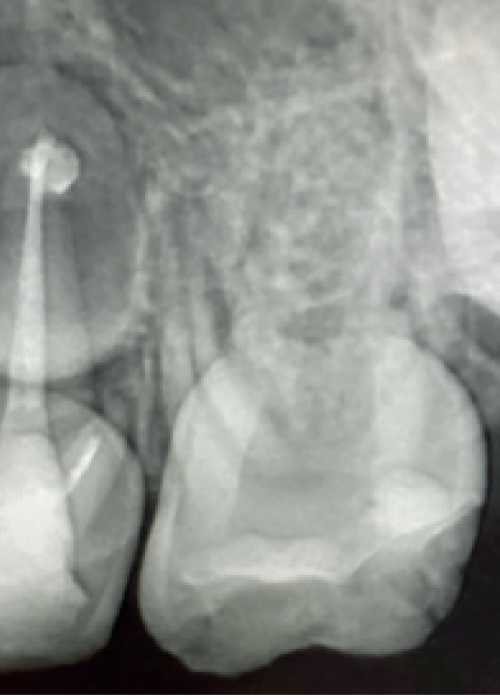

Dentinogénesis Imperfecta y Displasia Dentinaria. A propósito de un caso